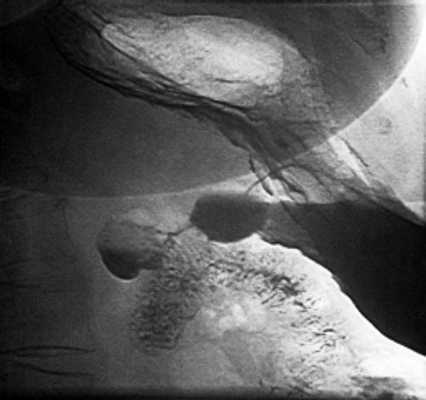

При рентгеноскопии желудка и двенадцатиперстной кишки: акт глотания не нарушен. Пищевод свободно проходим, определяется значительных размеров (до 7 см) грыжа пищеводного отверстия диафрагмы с выраженным рефлюкс-эзофагитом и забросом содержимого желудка в дистальный отдел пищевода, увеличивающаяся в размерах в положении лежа на животе. Желудок обычно расположен, натощак содержит слизь и жидкость. Складки слизистой утолщены, извиты, по задней стенке и большой кривизне в кардиальном отделе образуют зубчатость. Привратник свободно проходим, отмечается пролабирование слизистой желудка в луковицу двенадцатиперстной кишки. В нисходящей ветви петли двенадцатиперстной кишки определяется дивертикул на ножке размером 3 см с большим количеством слизи в нем (рис. 2). Луковица двенадцатиперстной кишки раздражена, бариевая взвесь очень быстро проходит ее, отмечается обратный заброс бариевой массы в желудок. Заключение: скользящая грыжа ПОД. Рефлюкс-эзофагит. Гастрит. Дуоденит. Дуоденогастральный рефлюкс. Дивертикул петли двенадцатиперстной кишки с признаками дивертикулита. От проведения ЭГДС пациентка категорически отказалась.

Рис. 2. Рентгенограмма дивертикула петли двенадцатиперстной кишки.

Рассматриваемый случай интересен тем, что большой дивертикул двенадцатиперстной кишки при ультразвуковом исследовании симулировал кисту поджелудочной железы. Кисты (псевдокисты) поджелудочной железы встречаются значительно чаще дивертикулов, поэтому вполне естественно заключение о наличии у больной кисты. Однако отсутствие указаний в анамнезе на острый или хронический панкреатит, неудачная попытка проследить связь выявленного жидкостного образования с головкой поджелудочной железы при полипозиционном исследовании, локальное утолщение дуоденальной стенки позволили высказать предположение о возможной прочей патологии и назначить дообследование.